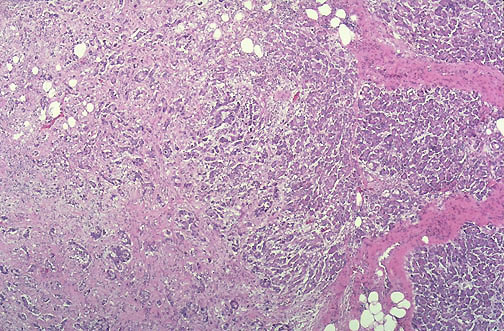

At low power there is an adenocarcinoma of the pancreas seen at the left, with normal pancreas at the right. A risk factor for pancreatic adenocarcinoma is smoking. There is a weaker association with diabetes mellitus and chronic pancreatitis.